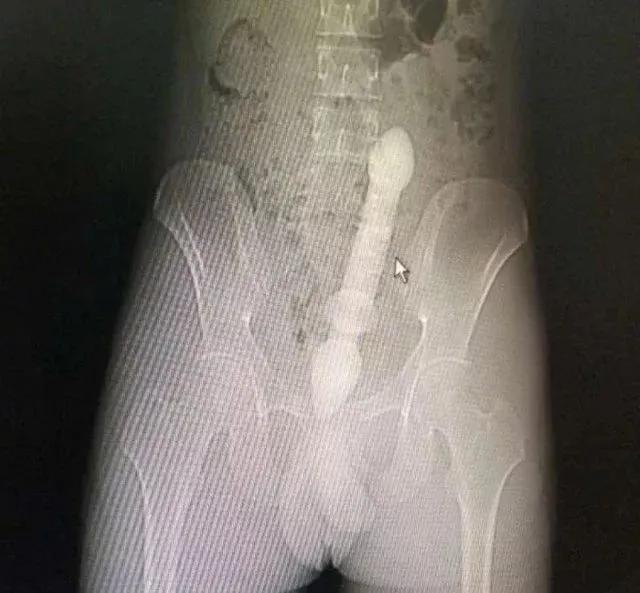

医生会通过一系列检查如直肠指诊、X线来确定体内的异物是什么,在什么位置,这一点非常关键,因为只有搞清楚里面的真实情况,医生才能找到合适的方法把异物取出。